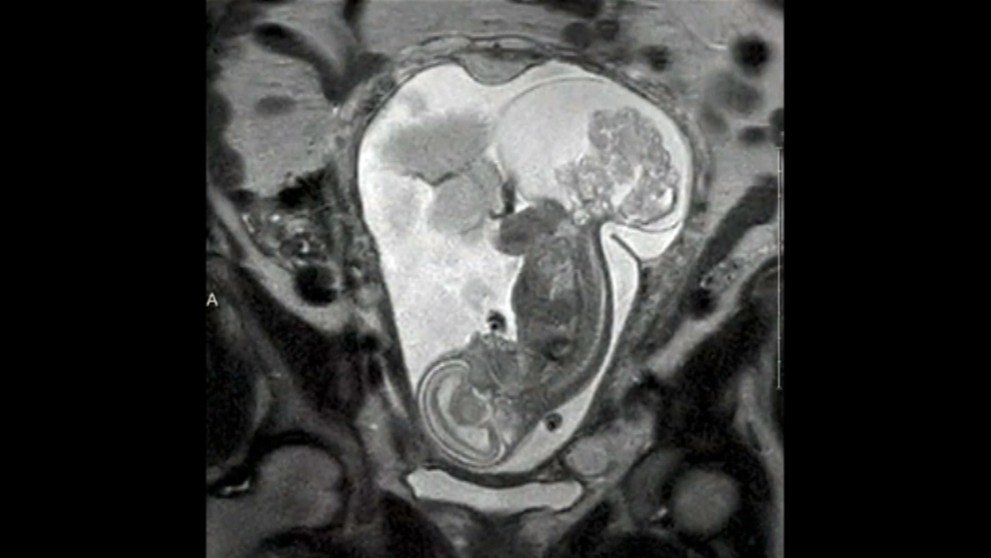

Dievčatko sa narodilo dvakrát. Lekári zistili matke v 16. týždni tehotenstva pri rutinnom ultrazvuku, že na plode je tumor. Nádor rástol a dieťa by skôr či neskôr zabil.

Margaret mala na výber. Buď by prerušila tehotenstvo, alebo by podstúpila operáciu, pri ktorej by jej vybrali dieťa z maternice. Keďže žena pôvodne čakala dvojčatá, ale jedno neprežilo, vybrala si druhú možnosť.

„Bolo to veľmi ľahké rozhodovanie. Chceli sme jej dať šancu na život," povedala matka pre denník DailyMail. Operáciu podstúpila v 24. týždni tehotenstva. Nádor bol v tom čase takmer rovnako veľký ako dieťa. Zákrok trval 5 hodín a dieťa bolo mimo tela matky 20 minút.

Po úspešnej operácii dieťa vložili naspäť do matkinej maternice a tú zašili. Dievčatko sa narodilo 12 týždňov po zákroku, keď matka bola 36. týždni cisárskym rezom. Po narodení vážila 2, 5 kg.

Dievčatko podstúpilo ešte jednu operáciu v ôsmom dni. Lekári odstránili z jej tela posledné zvyšky tumoru, ktoré sa im nepodarilo odobrať pri prvom zákroku. Hneď ako sa Lynlee zotavila, rodičia si ju zobrali domov.